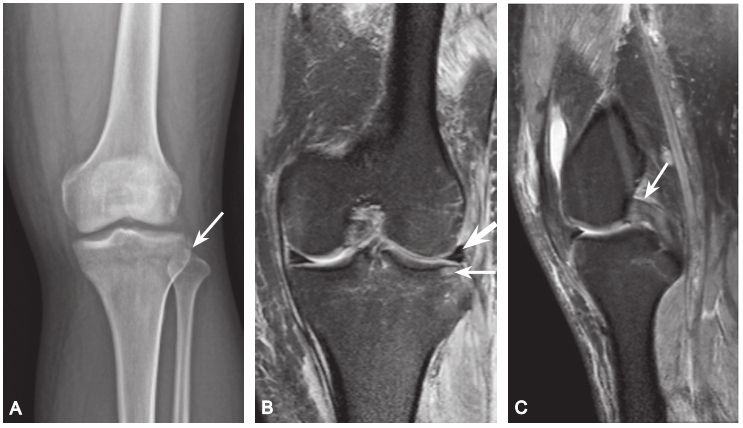

Segond 骨折:胫骨平台前外侧撕脱骨折,多因为下肢过度内翻加内旋暴力所致,常伴有前交叉韧带、内外侧半月板的损伤。

A. 膝关节 X 线前后位片,胫骨平台外侧缘撕脱椭圆形小碎骨片,长轴平行于胫骨,见侧囊征(箭头);B. 同一患者 MRI 冠状位 PDWI SPAIR 显示胫骨平台外侧缘撕脱骨折(细箭头),内外侧半月板内横形高信号,提示损伤(粗箭头);C. 矢状位 PDWI SPAIR 中间层面 PCL 显示肿胀,信号不均,提示 PCL 水肿,呈轻度损伤(箭头)